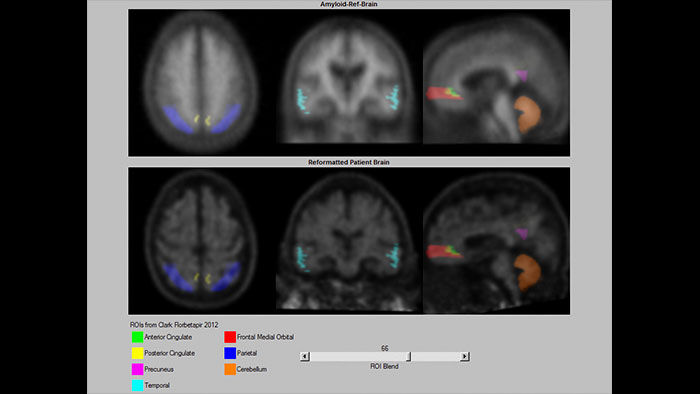

Assessing Amyloid plaque

The NM NeuroQ Amyloid analysis tool is designed to help clinicians to assess the presence or absence of Amyloid plaque in the brain. Provides quantitative analysis tools for Brain PET scans using NeuraCeq or Amyvid agents.